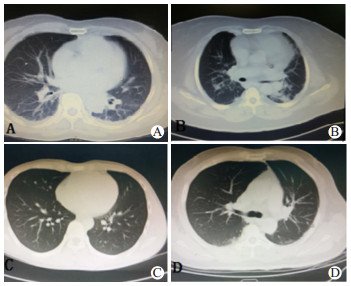

急性PQ中毒患者临床胸部CT显示,早期主要表现为肺纹理增粗、渗出实变和磨玻璃影; 中期主要表现为渗出实变、胸腔积液和间质改变; 晚期主要表现为渗出实变和间质改变[6]。比较入院首诊胸部CT显示,两组患者肺部CT出现肺纹理增粗、渗出实变和磨玻璃影等征象及肺CT阳性率均差异无统计学意义。比较两组患者中毒后72 h胸部CT结果,出现肺纹理增粗和磨玻璃影等征象及肺CT阳性率在组间差异有统计学意义,死亡组中毒后72 h出现渗出实变征象的比例明显高于存活组,但差异无统计学意义,见表 2和图 1。

| A:双肺纹理增粗伴磨玻璃影; B:双肺下野渗出实变伴少量胸腔积液; C:双肺下野轻度磨玻璃影; D:双肺下野少量渗出 图 1 急性百草枯中毒患者常见肺CT影像学表现 Fig 1 Common presentation of lung CT findings in PQ poisoning patients |